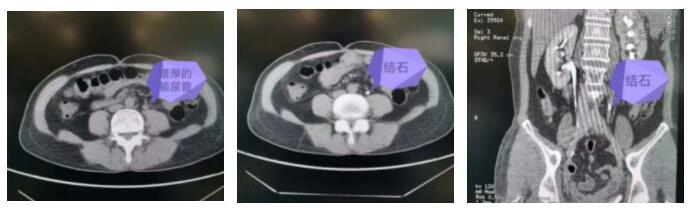

术前CT检查结石位置

新江苏·中国江苏网讯 (记者 孙骏 通讯员 李娜)52岁的戴女士近期在体检时发现左肾积水,左侧输尿管上段壁增厚,左侧输尿管中段结石。4月中旬,她来到南京医科大学附属明基医院泌尿外科门诊寻求治疗。

然而,戴女士多年前曾做过开放式子宫摘除手术,结石嵌顿时间较长,周围输尿管壁已增厚,可能结石已被增生的肉芽组织包裹,手术会有一定难度。为此张斌副主任医师所在治疗组在彭国辉主任医师指导下为戴女士制定了三套手术方案:经尿道经输尿管镜或软镜钬激光碎石,经皮肾微造瘘顺行输尿管软镜碎石以及最后考虑选择的开放取石手术。

很快,彭国辉主任医师确认最佳穿刺点,通过B超引导穿刺定位,顺利穿刺目标肾盏,放置安全导丝,逐级扩张至16F经皮肾微通道,沿通道置入输尿管软镜,探查发现输尿管中上段扩张水肿、粘膜表面充满大量滤泡,结石周围肉芽组织增生,有2枚结石嵌顿在增生的肉芽组织内,大小约6mm,形状不规则,用钬激光将结石击碎,并注入水将碎石向输尿管下段冲洗,同时用软镜扩张输尿管下段并将碎石推送入膀胱内,这样患者就可以通过术后排尿将结石碎片排出体外。